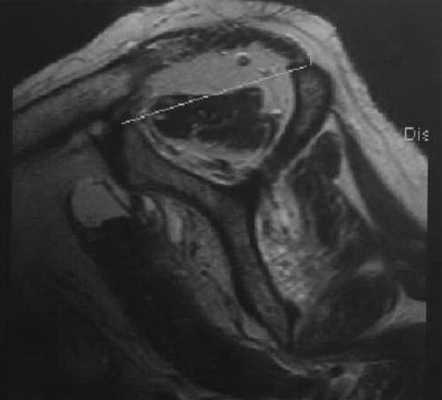

Артропатия при разрыве вращательной манжеты. Сагиттальная МРТ. Выраженный плечевой артрит. Выраженная атрофия надостной мышцы и пограничный положительный «признак касательной» (касательная к клювовидному отростку и ости лопатки не пересекает брюшко надостной мышцы).